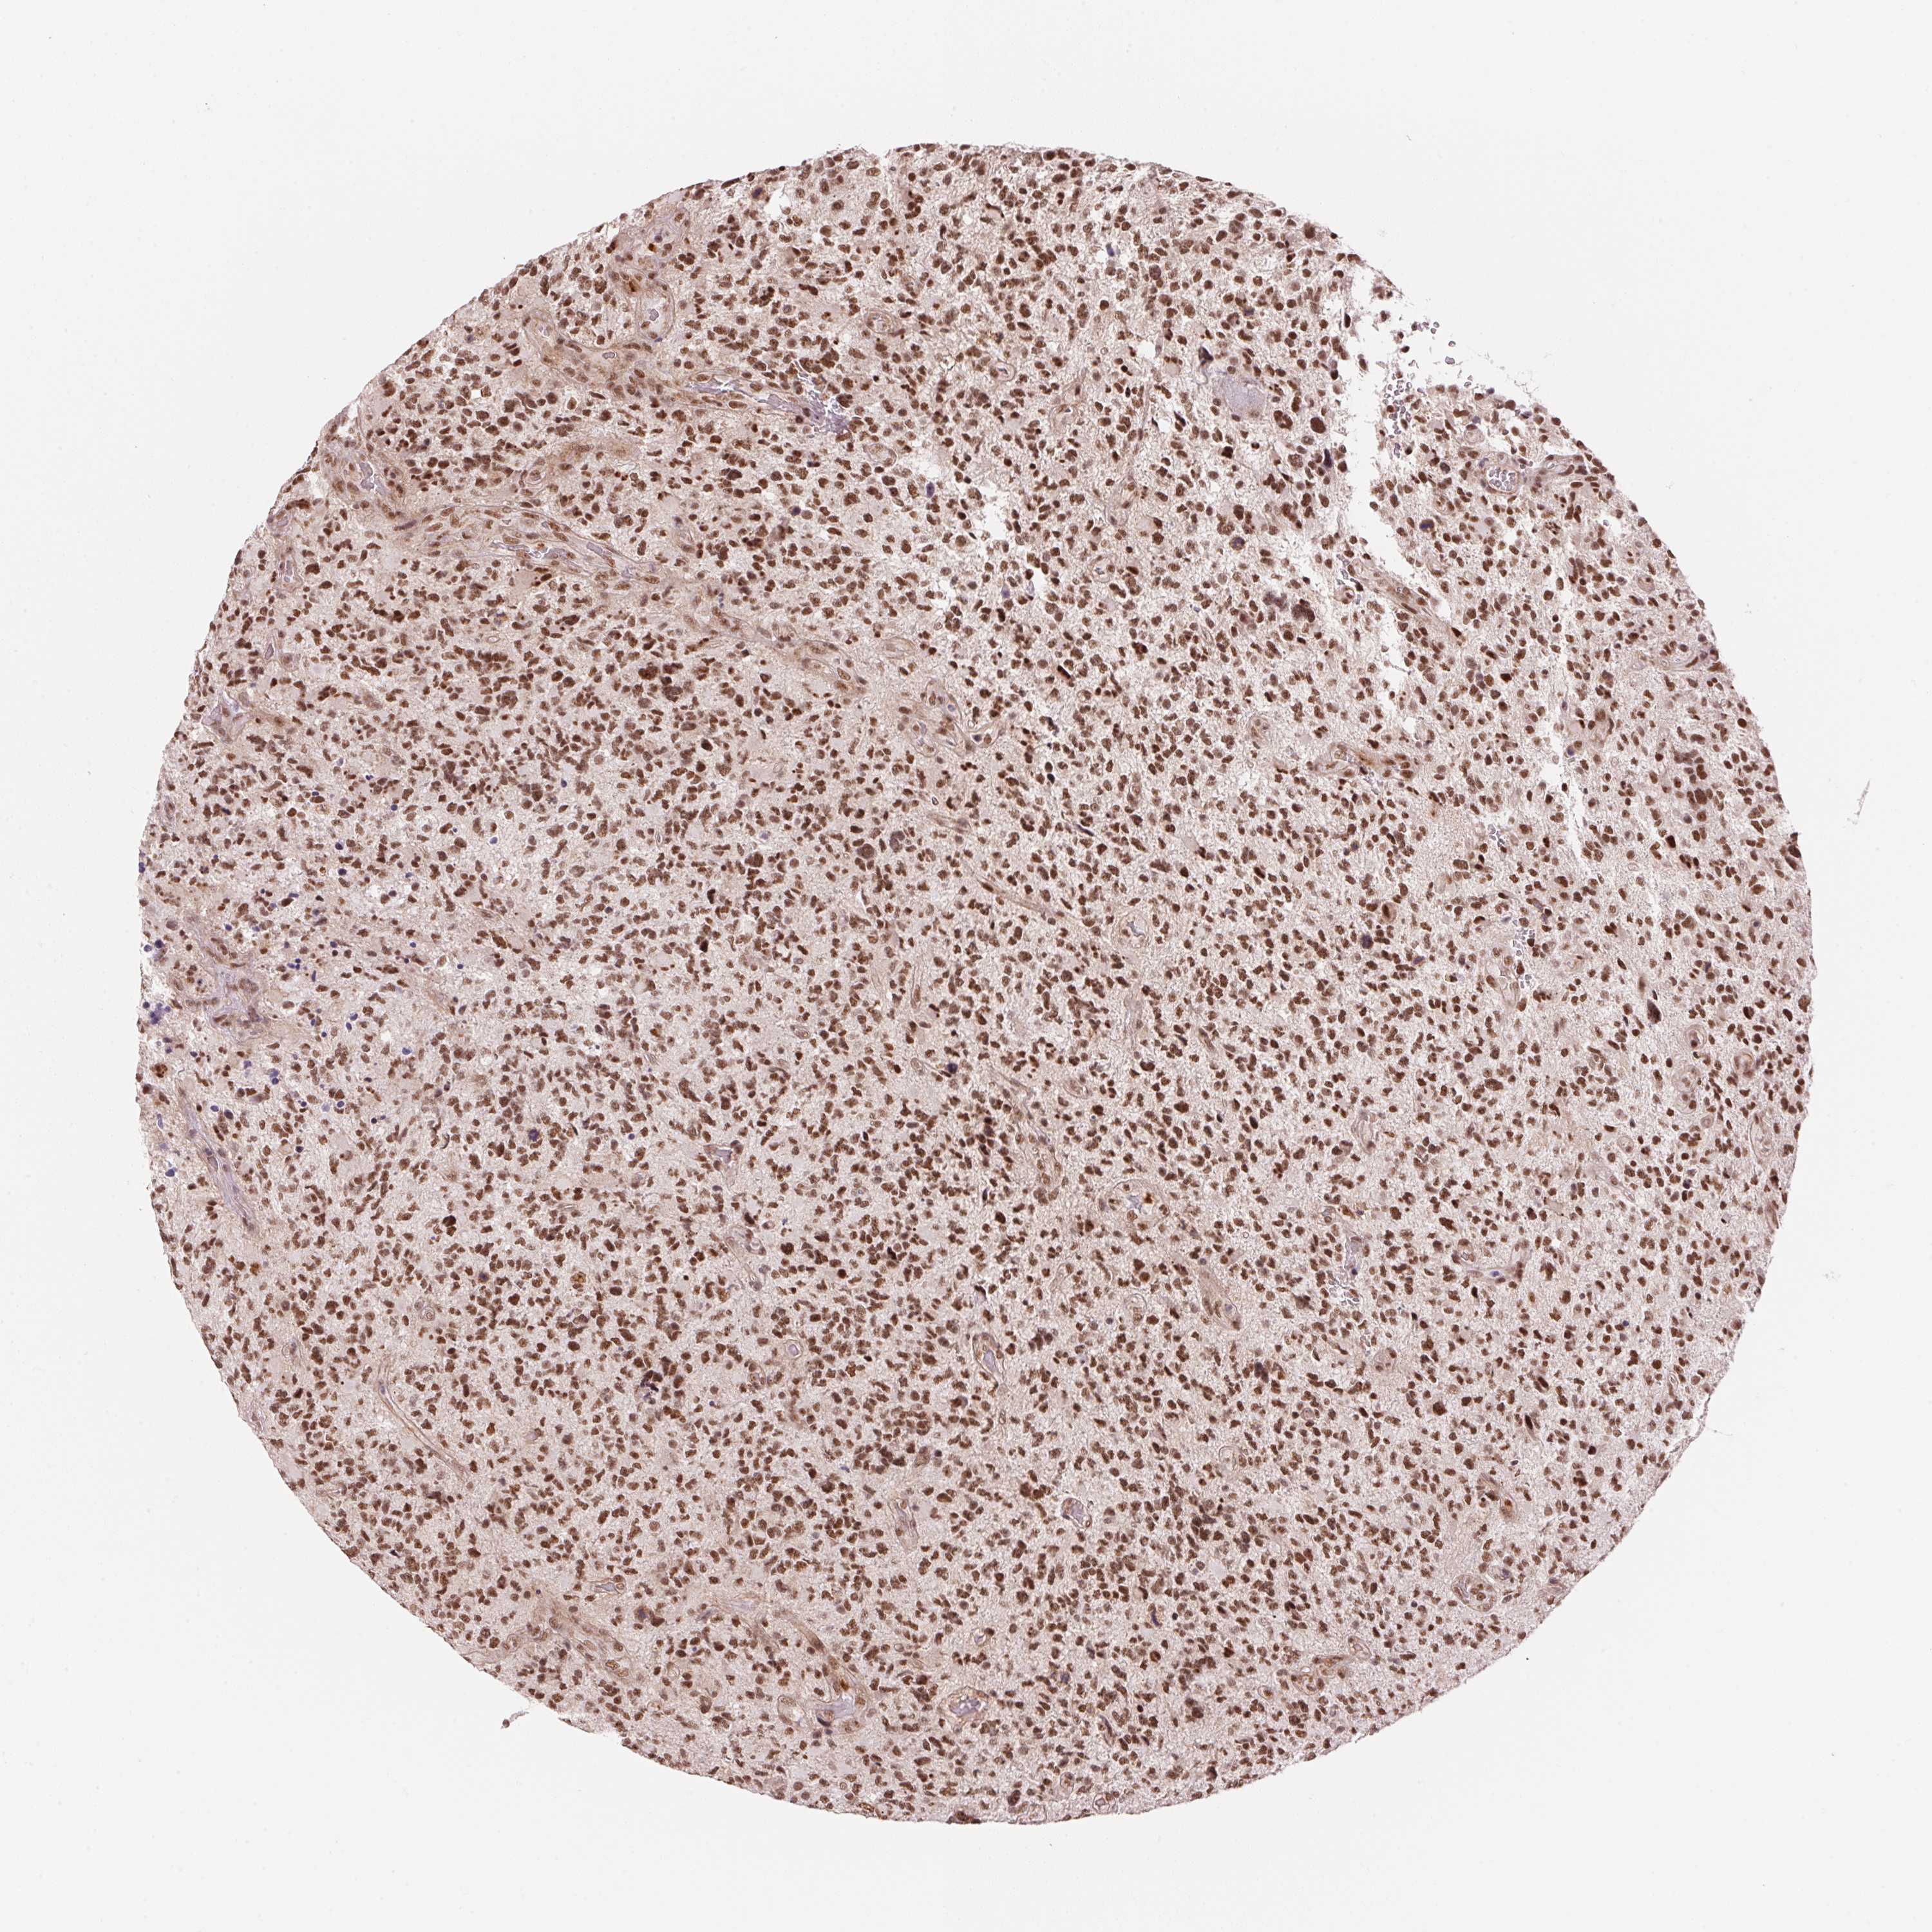

GLIOMA - Protein expressioni

A mouse-over function shows sample information and annotation data. Click on an image to view it in a full screen mode. Samples can be filtered based on level of antibody staining by selecting one or several of the following categories: high, medium, low and not detected. The assay and annotation is described here.

Note that samples used for immunohistochemistry by the Human Protein Atlas do not correspond to samples in the TCGA dataset.

Antibody stainingi

Antibody staining in the annotated cell types in the current human tissue is reported as not detected, low, medium, or high, based on conventional immunohistochemistry profiling in selected tissues. This score is based on the combination of the staining intensity and fraction of stained cells.

Each image is clickable and will lead to virtual microscopy that enables deeper exploration of all samples and also displays staining intensity scores, fraction scores and subcellular localization as well as patient and tissue information for each sample.

Antibody HPA056820

Antibody HPA063147

Staining

High

Medium

Low

Not detected

Intensity

Strong

Moderate

Weak

Negative

Quantity

>75%

75%-25%

<25%

None

Location

Nuclear

Cytoplasmic/membranous

Cytoplasmic/membranous,nuclear

Glioma, malignant, Low grade

Glioma, malignant, High grade